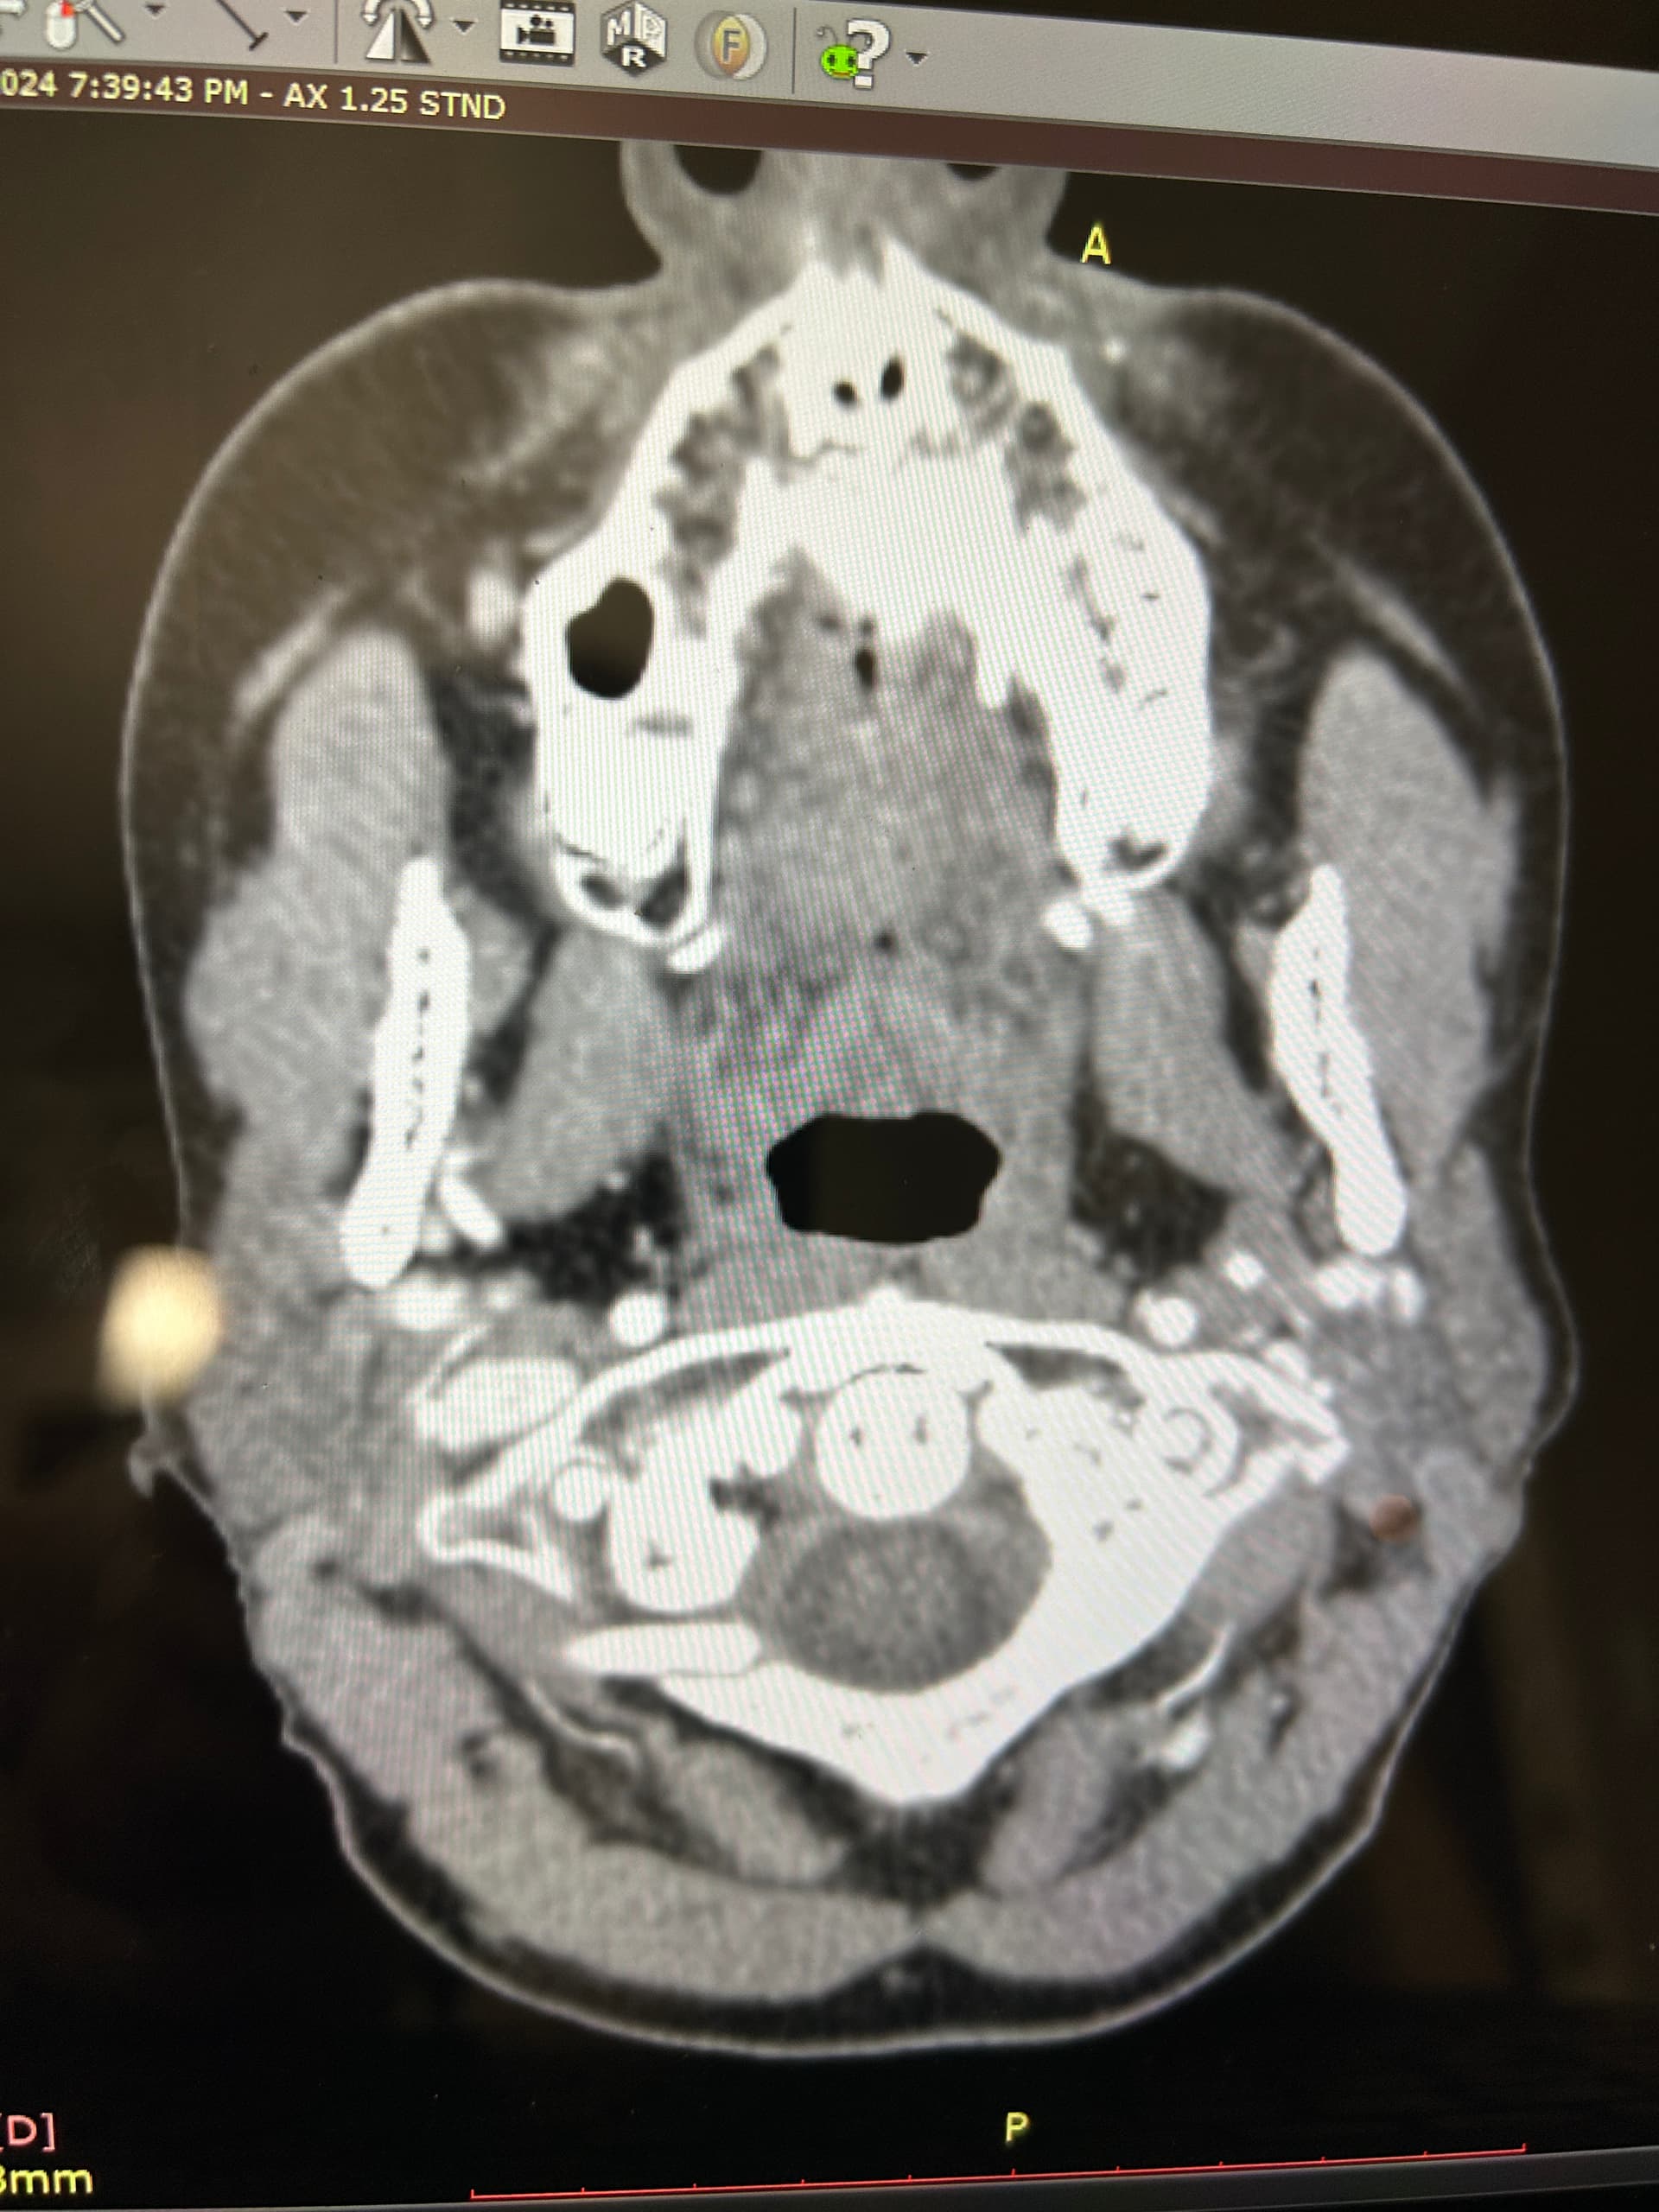

I’ve uploaded some photos. Some are repetitive but I know some in this group are skilled in reading these.

I also added some 3D photos. My left JV looks extremely narrow at around C3. Does anyone else see that?

@Luckee7 - I’ve marked some vascular structures that are above & beneath your C1 vertebra that I haven’t seen before in other imaging so am not sure what they are or if they could be involved in causing symptoms. Those above C1 appear to be “sitting” on it which appears to be causing some minor compression of those sections. They could be collateral veins, & if so, then they’re likely contributing to skull base/occipital pain.